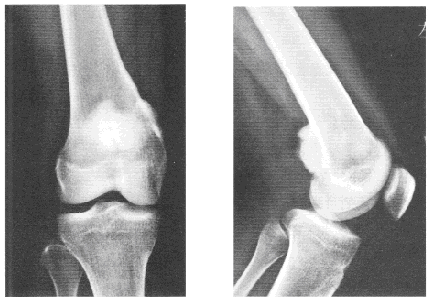

患者女,31岁。右膝后侧疼痛3年,加重3个月。患者3年前无明显诱因出现右膝后侧疼痛,尤以下蹲时最为明显,为间断性,与运动无关,休息后可缓解,未做诊治。3个月前疼痛逐渐加重,右膝屈伸活动轻度受限,于当地医院就诊,拍片发现右股骨下端后侧肿物,如图。无发热等全身症状,既往无外伤史。查体:右膝无肿胀,皮肤不红,无压痛点,膝关节屈曲轻度受限。血常规和血生化检查正常。